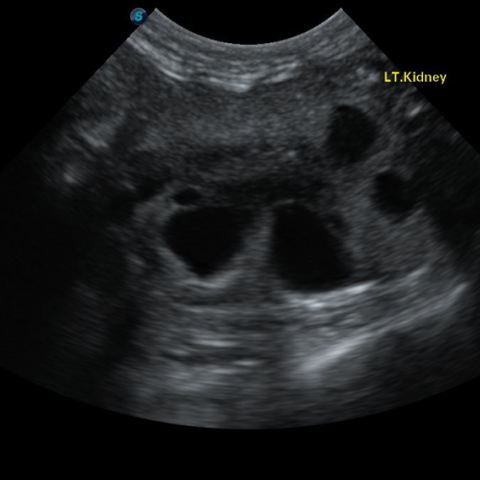

´Ù³¶¼º½ÅÀ庴

(PKD, Polycystic Kidney Disease)(Triaditis)

´Ù³¶¼º½ÅÀ庴À̶õ, ½ÅÀå¿¡ ´Ù¼öÀÇ ³¶Á¾ÀÌ ¹ß»ýÇϰí ÀÌ·Î ÀÎÇØ ½ÅÀå ±â´ÉÀÌ ÀúÇÏµÇ¸é¼ ¼¼È÷ ¸¸¼º ½ÅºÎÀüÀ¸·Î ÁøÇàµÇ´Â ÁúȯÀÔ´Ï´Ù. ÁÖ·Î Æä¸£½Ã¾È, È÷¸»¶ó¾á °°Àº ´ÜµÎÁ¾ °í¾çÀ̵鿡°Ô¼ ³ªÅ¸³ª´Â À¯Àüº´ÀÇ ÇϳªÀ̸ç, ´Ù³¶¼º½ÅÀåÀ» °¡Áø °í¾çÀ̵éÀº Æò±Õ 4¼¼¿¡ ÀÌ¹Ì ½ÅÀå ±â´ÉÀÌ ¼Õ»óµÇ±â ½ÃÀÛÇÑ´Ù°í º¸°íµÇ°í ÀÖ½À´Ï´Ù. µû¶ó¼ ÀÌ·¯ÇÑ Á¾·ùÀÇ °í¾çÀ̵éÀÇ °æ¿ì ºñ±³Àû ¾î¸° ¿¬·ÉºÎÅÍ Áö¼ÓÀûÀ¸·Î ½ÅÀå ±â´ÉÀ» ¸ð´ÏÅ͸µ ÇÏ´Â °ÍÀÌ ÇÊ¿äÇÕ´Ï´Ù. ¶ÇÇÑ ½ÅÀå »Ó ¾Æ´Ï¶ó ÁÖº¯ Àå±âÀÎ ºñÀå, °£, ÃéÀå¿¡µµ ³¶Á¾ÀÌ »ý±â¸é¼ À̵é Àå±âµµ ¹®Á¦°¡ µÉ ¼ö ÀÖÀ¸¹Ç·Î Á¤±âÀûÀÎ °Ç°°ËÁøÀ» ÅëÇØ °í¾çÀÌÀÇ °Ç° »óŸ¦ È®ÀÎÇÏ´Â °ÍÀÌ ÁÁ½À´Ï´Ù.